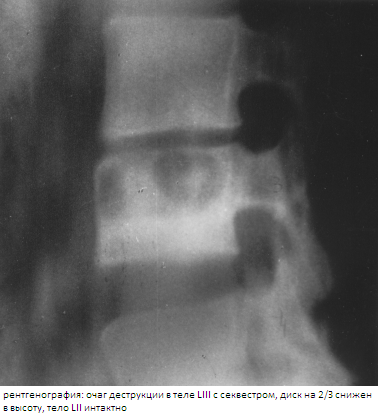

Всем пациентам с подозрением на туберкулезный спондилит рекомендуется выполнять МРТ для первичной и ранней диагностики. Однако рентгенодиагностика при туберкулезе позвоночника наиболее часто применяемый метод диагностики (после клинического) при этом диагностика спондилита, как правило, происходит на стадии контактной деструкции позвонков. Рентгенограммы пораженного отдела снимают в двух взаимно перпендикулярных проекциях: прямой и боковой. В позвоночнике трудно выявить небольшую степень остеопороза вследствие его непарности; кроме того, он прикрыт рядом органов различного кровенаполнения и различной воздухоносности, поэтому самым ранним признаком туберкулезного спондилита становится сужение межпозвонковой щели, свидетельствующее о нарушении целости межпозвонкового хряща и поражении тела позвонка. Сужение межпозвонковой щели на прямой рентгенограмме может оказаться ложным; истинное сужение видно как на прямом, так и на боковом снимке.

На основании проведенного анализа рентгенограмм и КТ и МРТ позвоночника при туберкулезном спондилите по характеру деструкции выделены 3 основных вида: 1) очаговая деструкция в телах позвонков; 2) образование межтелевой костной каверны с секвестрами или казеозными массами, периферические отделы тел при этом сохранены и образуют своеобразную «костную коробку» вокруг полости деструкции; 3) плоскостная контактная деструкция, когда смежные отделы тел разрушены равномерно по всей площади. По глубине деструкции тел выделено 4 варианта разрушения позвонков: 1) тела позвонков разрушены поверхностно и до 1/3 высоты; 2) тела позвонков разрушены на 1/2 или 2/3 высоты (встречался наиболее часто); 3) субтотальное и тотальное разрушение позвонков; 4) деструкция по типу кариеса. При вовлечении в процесс большого числа позвонков наблюдалось сочетание видов и вариантов деструкции. В редких случаях атипичного течения туберкулезного спондилита характер деструкции не укладывался в указанные виды.